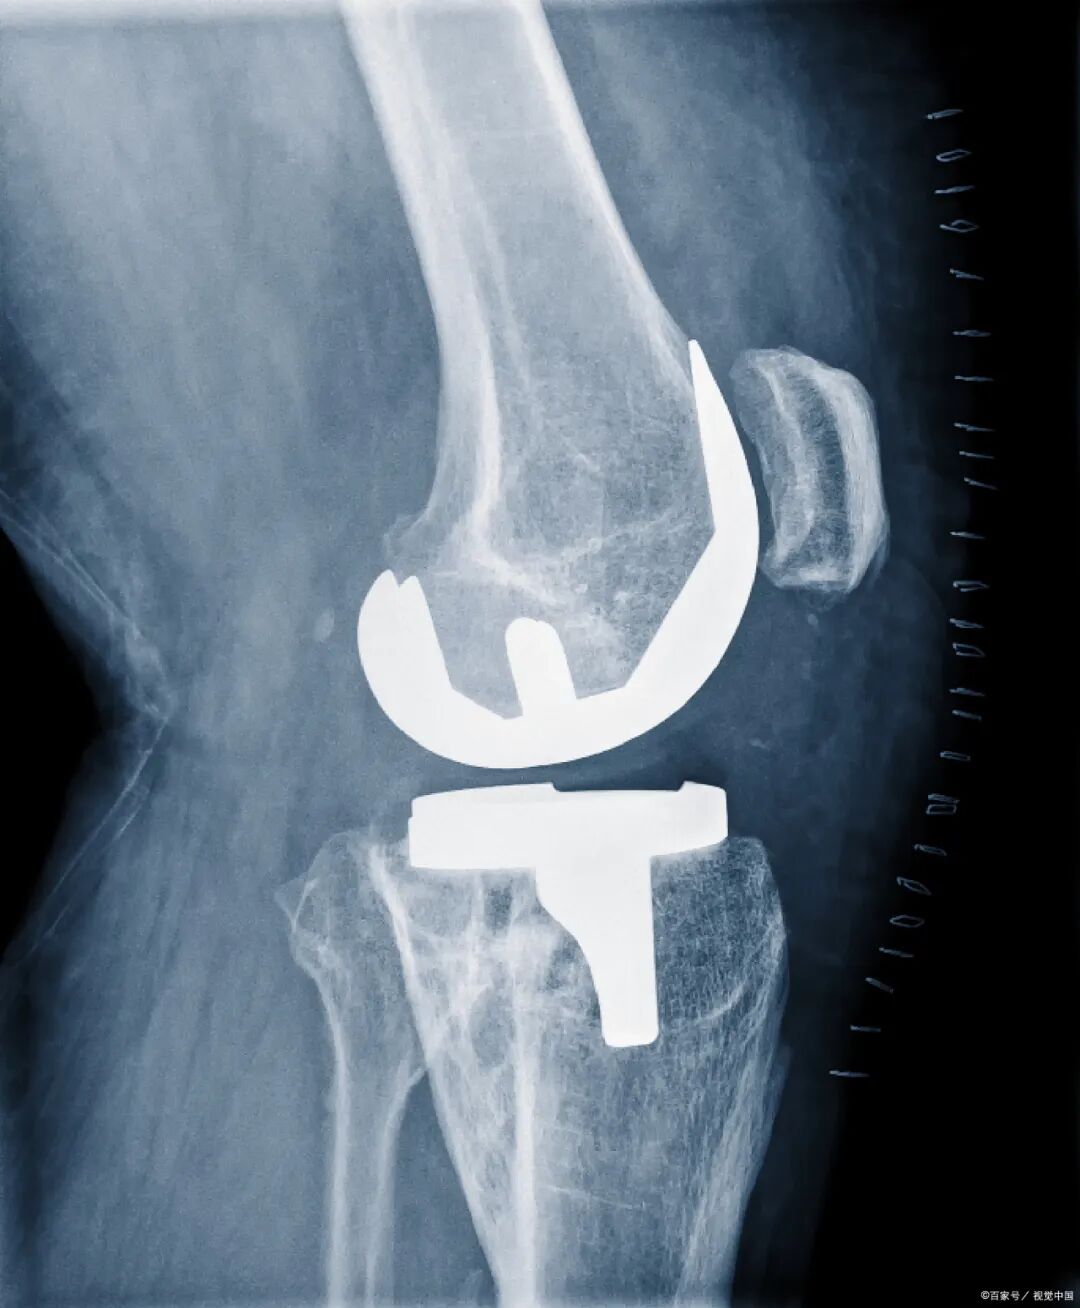

生物相容:经临床验证,UPE在人体内20年不会出现降解现象,所以在医疗领域有很大的发展潜力,如制作人工关节等植入体。

人工关节:因为具有优秀的生物相容性和耐磨性,UPE成为制作人工关节的最优选,这种材料在医疗领域的利用价值非常广泛,前景无限。